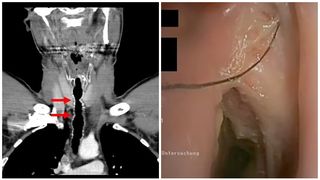

După ce au aflat ce simptome are, medicii au efectuat o procedură care le-a permis să introducă o cameră video de mici dimensiuni pe căile respiratorii ale pacientului și au descoperit că acestuia îi crescuseră mai multe fire de păr într-o zonă din gâtul lui pe care acesta suferise anterior o operație.

Bărbatul, originar din Austria, a fost diagnosticat cu creșterea părului endotraheal, sau creșterea părului în gât.

La fiecare control medical, în gâtul omului se regăseau șase până la nouă fire de păr de aproximativ 5 centimetri, unele reușind să treacă prin cutia vocală și să-i treacă în gură.

Ulterior, această secțiune în trahee a fost închisă folosind cartilaj și piele de la ureche. În zona operată i-a apărut păr în gât care a continuat să apară an de an până când pacientul s-a lăsat de fumat.